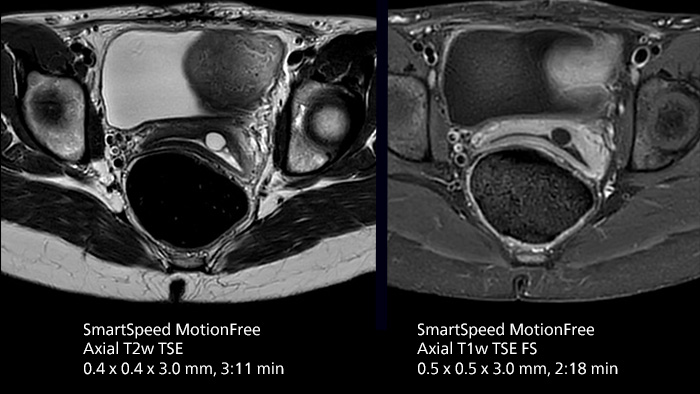

- Motion robustness and high-resolution uterus protocol

- Motion robustness and high-resolution uterus protocol